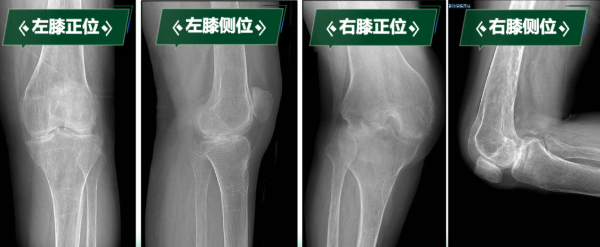

“真不敢相信,我能站起来,还能走路……”刘阿姨因罹患类风湿性关节炎多年,骨质受到严重侵蚀,导致双膝关节逐渐纤维性强直,更加棘手的是,双膝强直于两个极端体位,左膝关节无法弯曲,像“木棍”一样始终处于伸直状态;右膝长期处于极重度屈曲挛缩90度无法伸直。 这种“一伸一屈”的特殊畸形,导致无法正常坐立、行走,生活无法自理,身心承受巨大痛苦……

类风湿性关节炎整体发病率0.5~1%,约有10-20%会出现关节强直,关节致残率高达43.48%。“临床上一般超过30度的屈曲挛缩畸形定义为重度屈曲挛缩畸形,这种超过90度极重度屈曲挛缩非常少见,再加上‘一曲一伸’两种极端位置的强直,集中在同一个病人身上,手术难度和风险会成倍增加。”曹晓瑞副主任医师讲到。

下肢处于功能“锁死”状态的刘阿姨,不仅被剥夺了行走能力,还导致严重肌肉萎缩、骨质疏松,生活质量急剧下降,手术是帮助她重新站起来的唯一途径。科室高度重视,经多学科会诊讨论,制定周密治疗规划。曹晓瑞副主任医师团队分析术前影像学资料,精确评估膝关节骨质破坏、关节融合及周围软组织条件。

手术关键难点在于精准截除融合骨组织、获得屈伸间隙平衡、恢复下肢力线、确保韧带平衡以重建膝关节功能。团队凭借丰富经验和娴熟技术,成功实施双侧人工全膝关节置换术。术后影像学检查显示,假体位置精准,下肢力线完美纠正,原本僵硬关节被活动自如的人工关节取代,患者功能恢复理想,能正常行走,生活质量显著改善。